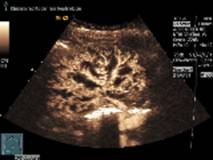

Die kontrastverstärkte Ultraschalluntersuchung

einer Transplantatniere zeigt das Anfluten

des Ultraschallkontrastmittels (hell)

mit der Darstellung der Gefäßarchitektur

in der transplantierten Niere.

Quelle: Dr. Konrad Stock, Nephrologischer Ultraschall,

Klinikum rechts der Isar